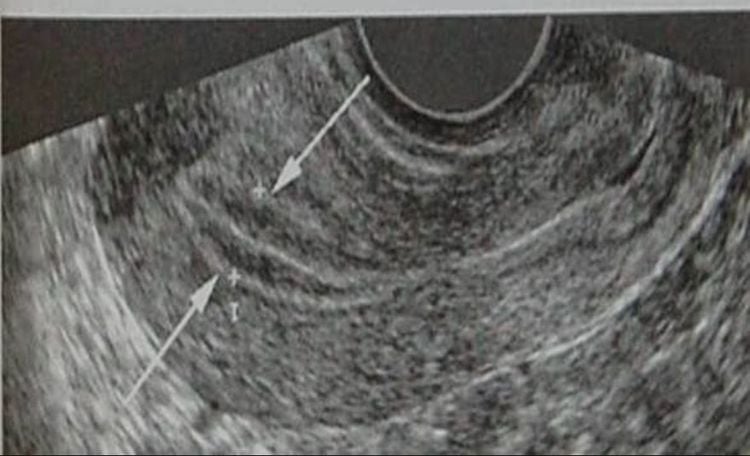

Niêm mạc tử cung còn gọi là nội mạc tử cung là lớp tế bào lót ở mặt trong tử cung, dưới tác động của nội tiết tố nữ niêm mạc tử cung thay đổi dày mỏng theo chu kỳ kinh nguyệt, tuổi tác và khi mang thai. Niêm mạc tử cung có vai trò quan trọng trong việc thụ thai, mang thai.

Trong suốt chu kỳ kinh nguyệt dưới tác động của hormone niêm mạc tử cung tăng sinh, đến khoảng giữa chu kỳ kinh nguyệt niêm mạc tử cung dày khoảng 8-12mm giai đoạn này xảy ra hiện tượng rụng trứng. Nếu có hiện tượng thụ thai xảy ra ở khoảng thời gian rụng trứng thì cơ thể sản xuất một lượng lớn hormone nữ làm cho niêm mạc tăng sinh mạnh mẽ giúp cho trứng đã thụ thai vào làm tổ.

- Giai đoạn rụng trứng niêm mạc tử cung khoảng từ 8-12mm.

- Nửa cuối chu kỳ niêm mạc tử cung dày đến khoảng 12-16mm.

Nếu kinh nguyệt đến chậm kết hợp với niêm mạc tử cung dày trong khoảng từ 8-16mm thì đây là một dấu hiệu cho thấy bạn đã thụ thai. Thế nên khi niêm mạc tử cung dày khoảng 13mm thử que 2 vạch thì khả năng bạn đã mang thai và độ dày niêm mạc tử cung như thế này phù hợp để cho thai phát triển.